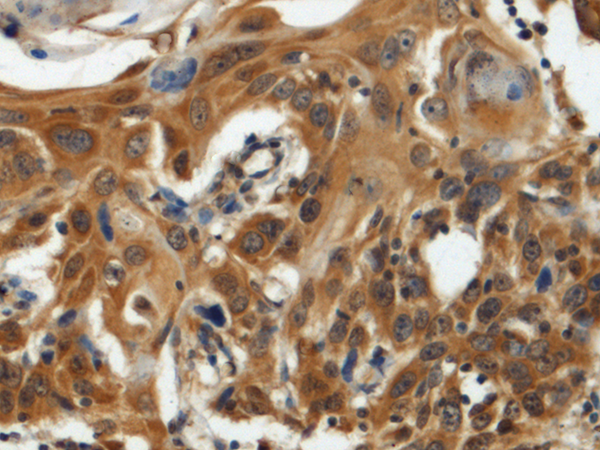

ELISA, IHC

IHC positive control:

Human esophagus cancer and Human tonsil

IHC Recommend dilution:

100-300